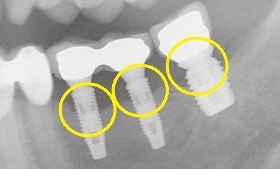

治療後,X光片。